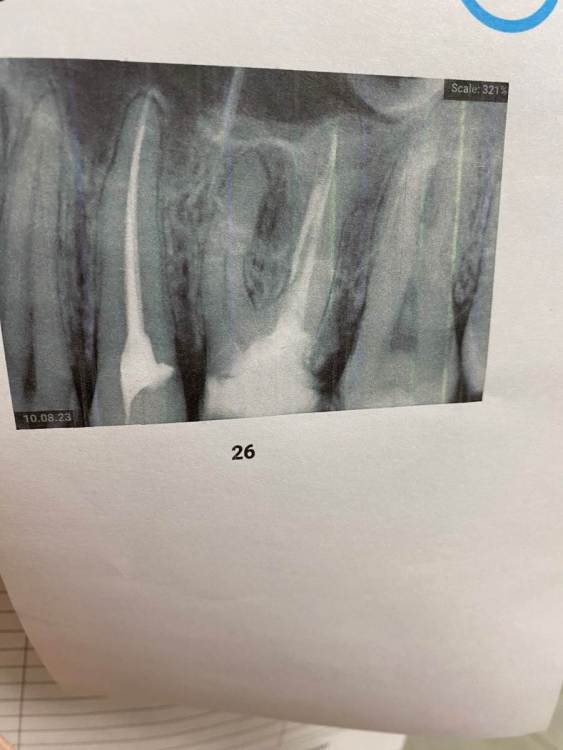

AlexB1 Опубликовано 10 августа, 2023 Поделиться Опубликовано 10 августа, 2023 Добрый вечер. Планировалась установка коронки на зуб, но после снимка врач сказала что показано удаление. Есть ли шанс сохранить зуб или только удаление? Ссылка на комментарий

Женька Опубликовано 10 августа, 2023 Поделиться Опубликовано 10 августа, 2023 @AlexB1 здравствуйте. Вам бы КЛКТ сделать для начала. По этому снимку оценивать очень сложно. Не всё так однозначно, как может казаться. Нужна дополнительная диагностика. 1 Ссылка на комментарий

DoctorT Опубликовано 11 августа, 2023 Поделиться Опубликовано 11 августа, 2023 16 часов назад, AlexB1 сказал: Добрый вечер. Планировалась установка коронки на зуб, но после снимка врач сказала что показано удаление. Есть ли шанс сохранить зуб или только удаление? Сделаете КТ (как выше док сказал), оценить состояние тканей вокруг корней, если все лечибельно, то нужно убрать старую пломбу, убрать инфицированный твердые ткани зуба и оценить еще здесь (сколько здоровых тканей осталось и как сильно зуб разрушен). На основании этого принять решение. Ссылка на комментарий